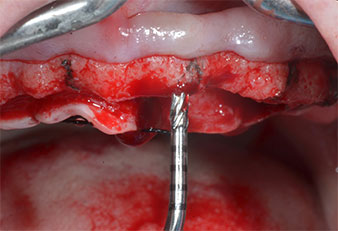

Un insert piézoélectrique diamanté de forme effilée (Piezomed I1) a été utilisé pour marquer les positions implantaires et effectuer la préparation pilote (Fig. 3). On a pris soin de travailler selon un mouvement ascendant et descendant, à puissance réduite, irrigation complète et basse pression (moins de 300g). Ensuite, un insert pilote (Piezomed I2A/I2P) a été utilisé pour l’agrandissement initial de 2mm du diamètre des sites implantaires (Fig. 4), suivi d’un insert de 3mm (Fig. 5).

En cas de densité osseuse élevée, il convient d’utiliser toute la gamme d’inserts, y compris les inserts intermédiaires Piezomed Z25P et Z35P afin d’élargir

les ostéotomies avant l’étape d'agrandissement suivante.

Dans le cas présent, les inserts Z25P et Z35P n’ont pas été utilisés car l’os postérieur était relativement mou

et l’intervention sur celui-ci a été aisée avec le I3A/I3P.

Compte tenu de la dureté relative de l’os (D2) à cet endroit, les sites recevant des implants de 10mm de long aux régions 11 et 21 ont été finalisés à l'aide d’une fraise de 4mm de diamètre, associée à un contre-angle chirurgical W&H WS-75 L, au moteur d'implantologie Implantmed de W&H ainsi qu’au module Osstell ISQ de W&H. En revanche, en raison de leur structure osseuse molle, les sites postérieurs ont été préparés en vue de l’obtention d’un diamètre final de 3mm à l'aide de l’insert Piezomed I3P. Les implants ont enfin été posés par voie transgingivale (Flap Less) pour obtenir l’ostéointégration dans un délai de trois mois (Figures 6-10). L'appareil existant a été maintenu sur quatre implants provisoires (Fig. 8).